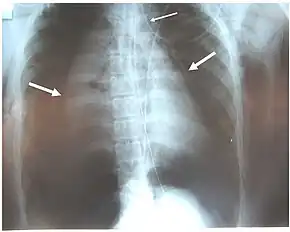

a)Collapsed right lung , left deviated trachea , and shifted heart b) chest illustrating collapsed right lung and shifted heart -

Chest x-ray is the initial imaging technique used to diagnose TBI.[17] The film may not have any signs in an otherwise asymptomatic patient.[15] Indications of TBI seen on radiographs include deformity in the trachea or a defect in the tracheal wall.[17] Radiography may also show cervical emphysema, air in the tissues of the neck.[2] X-rays may also show accompanying injuries and signs such as fractures and subcutaneous emphysema.[2] If subcutaneous emphysema occurs and the hyoid bone appears in an X-ray to be sitting unusually high in the throat, it may be an indication that the trachea has been severed.[4] TBI is also suspected if an endotracheal tube appears in an X-ray to be out of place, or if its cuff appears to be more full than normal or to protrude through a tear in the airway.[17] If a bronchus is torn all the way around, the lung may collapse outward toward the chest wall (rather than inward, as it usually does in pneumothorax) because it loses the attachment to the bronchus which normally holds it toward the center.[6] In a person lying face-up, the lung collapses toward the diaphragm and the back.[23] This sign, described in 1969, is called fallen lung sign and is pathognomonic of TBI (that is, it is diagnostic for TBI because it does not occur in other conditions); however it occurs only rarely.[6] In as many as one in five cases, people with blunt trauma and TBI have no signs of the injury on chest X-ray.[23] CT scanning detects over 90% of TBI resulting from blunt trauma,[3] but neither X-ray nor CT are a replacement for bronchoscopy.[6]